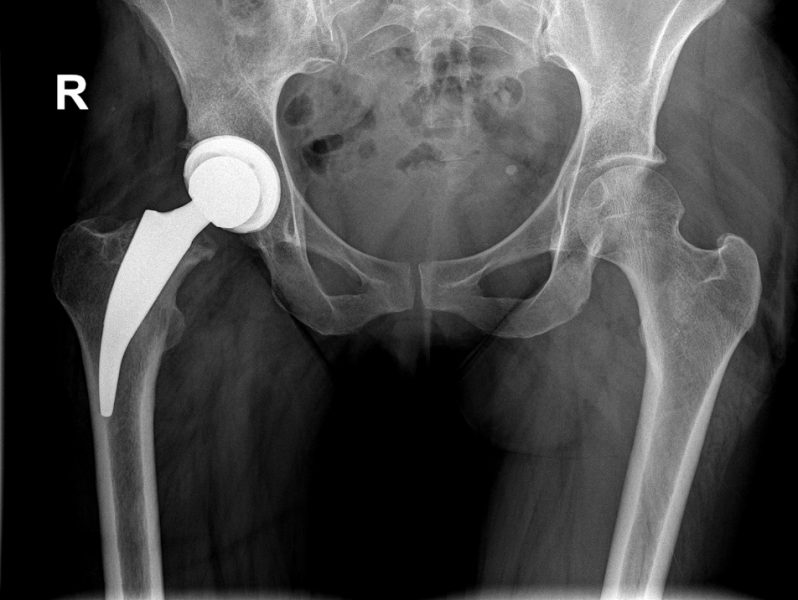

In unserer Abteilung werden primäre und Revisionsendoprothesen an Hüft –, Knie – und Schultergelenken durchgeführt.